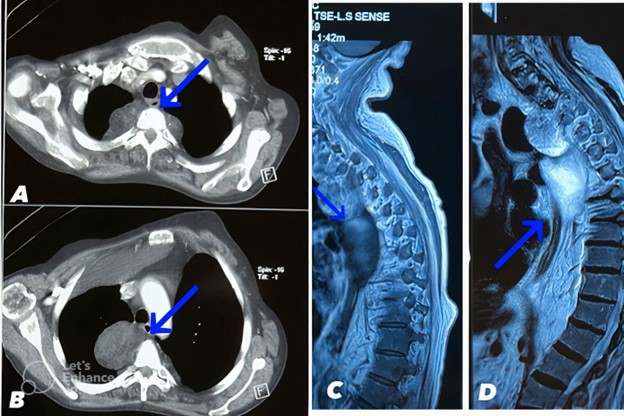

Abdominal and pelvic ultrasound identified right-sided pleural effusion (300-500 cc), leading to a pleural fluid tap under ultrasound guidance. The cytology of the pleural fluid showed several mature lymphomononuclear cells mixed with isolated mesothelial cells in the proteinaceous background. The analysis of the pleural fluid indicated that it was transudative with a lactate dehydrogenase (LDH) level of 95 IU/L, protein level of 2 g/dL, and glucose level of 126 mg/dL, confirming the patient's congestive heart failure (CHF). Contrast-enhanced chest CT reveals bilateral paravertebral masses with the larger mass on the right side measuring up to 66 x 46 mm. Both masses contain components of fat and soft tissue density with Hounsfield units ranging from -50 to -100 HU consistent with adipose tissue interspersed with soft tissue density regions of 20- 50 HU. The masses demonstrate heterogeneous enhancement following IV contrast administration. The right paravertebral mass causes mass effect with rightward tracheal deviation and narrowing of the right mainstem bronchus. The masses cause erosion and remodeling of the adjacent T5, T6, and T7 vertebral bodies. Mature adipose tissue comprising the bulk of the masses is identified as hypodense regions with Hounsfield units around -80 HU as indicated by blue arrows on CT images (Figure 2).

Figure 2. A and B: Contrast-enhanced chest CT scan reveals bilateral paravertebral masses (larger size on the right side) containing fat and soft tissue density and shows heterogeneous enhancement. The mature adipose tissue was indicated by blue arrows. C and D: Thoracic MRI in the sagittal plane demonstrated that paravertebral mass has heterogenous high T1 and T2 signal intensity. The mature adipose tissue was indicated by the blue arrow.

A biopsy of the right posterior mediastinum tissue, guided by a CT scan, revealed sheets of trilineage hematopoietic elements between adipose tissue, consistent with myelolipoma. There was no evidence of lymphomatous cells, tumoral lesions, or malignancy in the specimen. Thoracic magnetic resonance imaging (MRI) indicated multiple restricted enhancing masses in the bilateral paravertebral region, suggestive of extramedullary hematopoiesis or multiple neurofibromas. Paraclinical findings also indicated heart enlargement and pulmonary hypertension (40 mm). The significant right-sided pleural effusion could be attributed to congestive heart failure, and there were no intrapulmonary nodules or patchy densities.